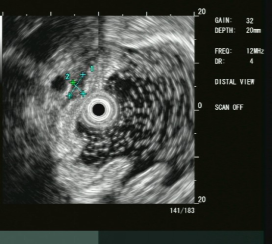

大型超声内镜下(EUS)胰腺占位性病变的FNA/FNB技术

内镜超声小探头行胃、肠道粘膜下隆起病变诊断

胃内粘膜下隆起,术前结合我科超声内镜,诊断考虑异位胰腺。

胃内粘膜下隆起,术前超声提示来源于固有肌层,术前判断需胃壁全层切除。